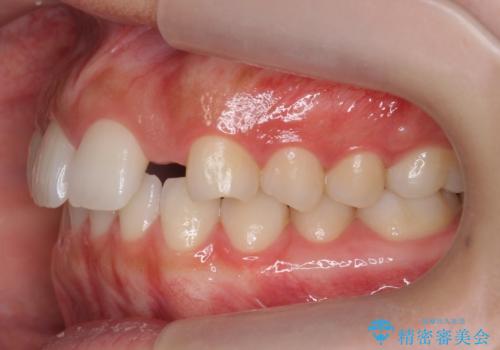

また、右の奥歯の関係も上が前にある状態で大きくずれていました。

臼歯関係は無理に1級にしようとすると抜歯が必要になります。

今回は左右とも1歯対2歯の関係であるため、それは変えずに前歯を可及的にひっこめて足りない部分をブリッジで補う治療としました。

奥歯の関係を完全に1級にするには右上の小臼歯の抜歯が必要でしたが、もともと左上の前歯が生まれつき少ないため今回は歯を抜かずに治療しています。